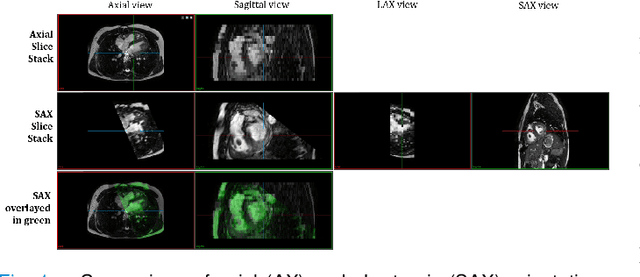

Abstract:Anisotropic multi-slice Cardiac Magnetic Resonance (CMR) Images are conventionally acquired in patient-specific short-axis (SAX) orientation. In specific cardiovascular diseases that affect right ventricular (RV) morphology, acquisitions in standard axial (AX) orientation are preferred by some investigators, due to potential superiority in RV volume measurement for treatment planning. Unfortunately, due to the rare occurrence of these diseases, data in this domain is scarce. Recent research in deep learning-based methods mainly focused on SAX CMR images and they had proven to be very successful. In this work, we show that there is a considerable domain shift between AX and SAX images, and therefore, direct application of existing models yield sub-optimal results on AX samples. We propose a novel unsupervised domain adaptation approach, which uses task-related probabilities in an attention mechanism. Beyond that, cycle consistency is imposed on the learned patient-individual 3D rigid transformation to improve stability when automatically re-sampling the AX images to SAX orientations. The network was trained on 122 registered 3D AX-SAX CMR volume pairs from a multi-centric patient cohort. A mean 3D Dice of $0.86\pm{0.06}$ for the left ventricle, $0.65\pm{0.08}$ for the myocardium, and $0.77\pm{0.10}$ for the right ventricle could be achieved. This is an improvement of $25\%$ in Dice for RV in comparison to direct application on axial slices. To conclude, our pre-trained task module has neither seen CMR images nor labels from the target domain, but is able to segment them after the domain gap is reduced. Code: https://github.com/Cardio-AI/3d-mri-domain-adaptation